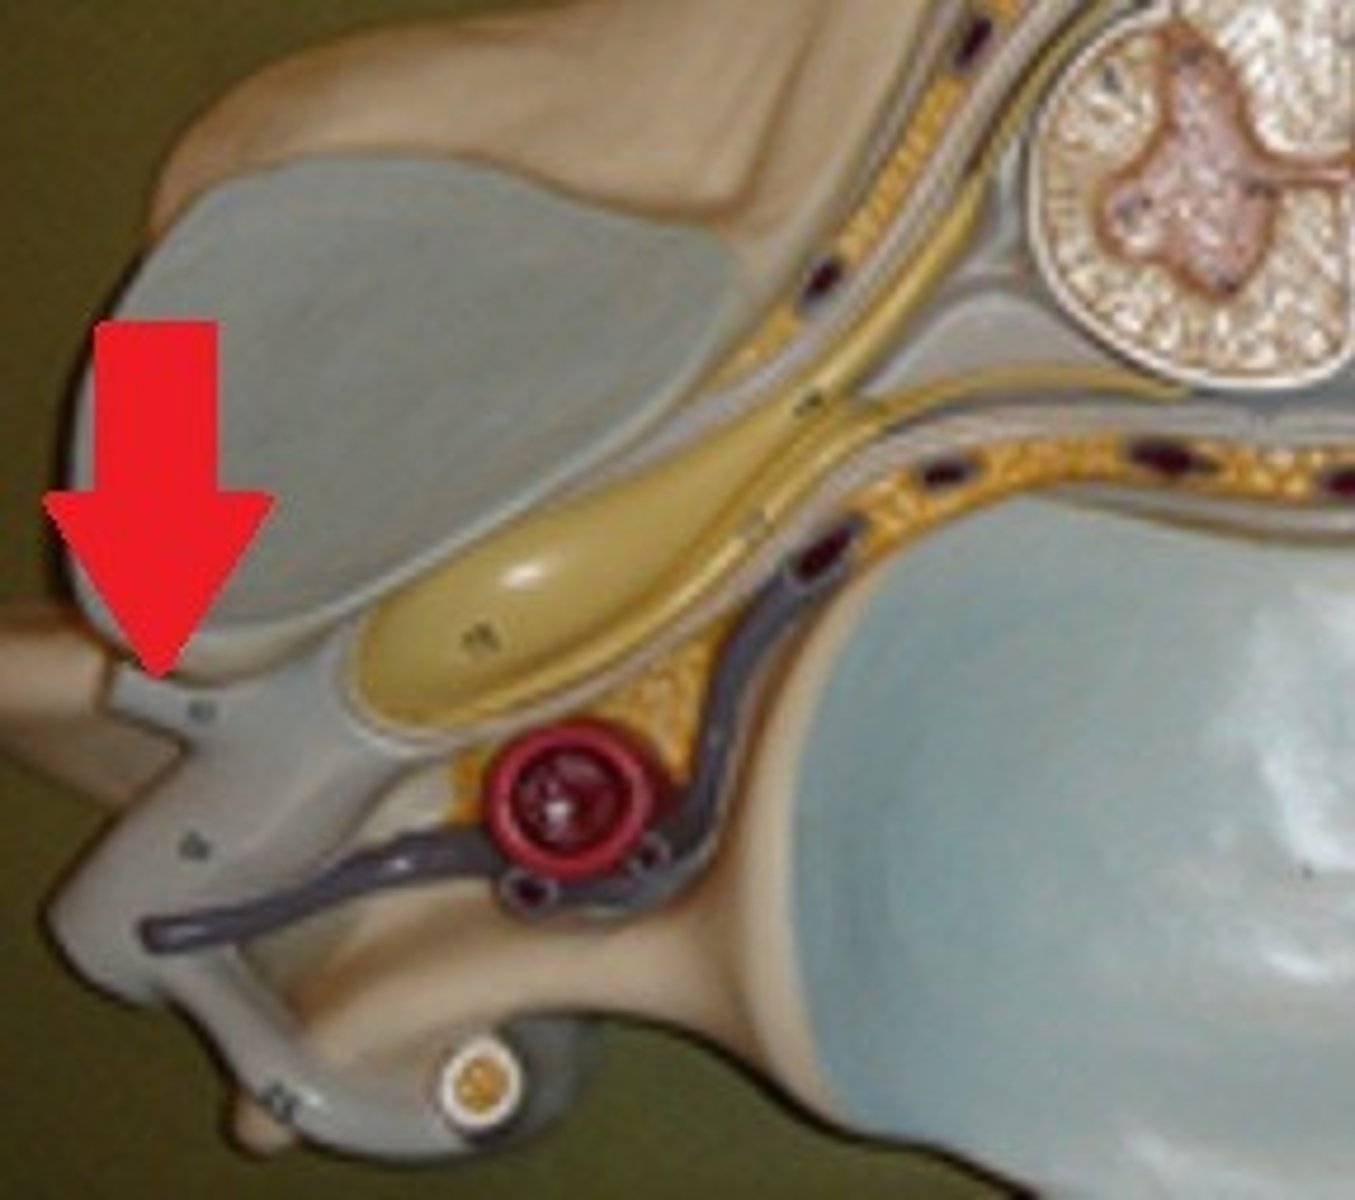

Dura mater

1

arachnoid mater

2

pia mater

3

epidural space

4

subdural space

5

subarachnoid space

6

red arrow